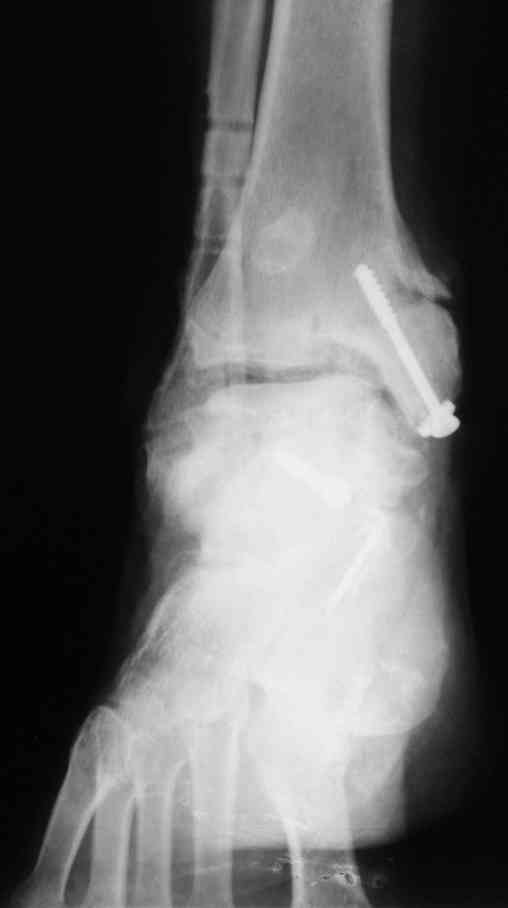

В Вашей ситуации мы произвели открытую репозицию и фиксацию металлоконструкциями. Все зажило первично, посттравматического дефартроза избежать не удалось. Пациент от артродезирующих операций в отдаленном периоде отказался.